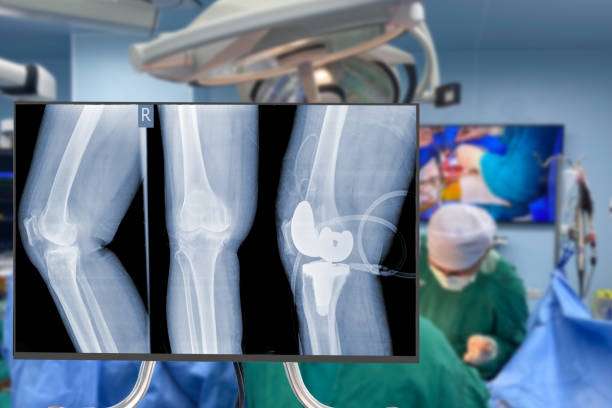

Knee Replacement Surgery for Enhanced Mobility at Maddadgar Foundation: Maddadgar Foundation provides comprehensive knee replacement surgery to improve mobility and reduce pain caused by knee damage. Our team of orthopedic surgeons offers personalized care and employs the latest surgical technology for faster healing. Regain your independence and enjoy a pain-free life with knee replacement surgery from Maddadgar Foundation.